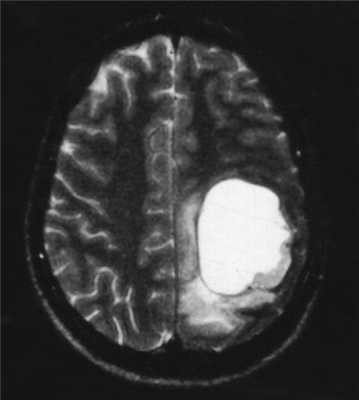

МРТ головного мозга. Астроцитома с большой реактивной кистой. Аксиальная Т2-зависимая и сагиттальная Т1-зависимая МРТ.